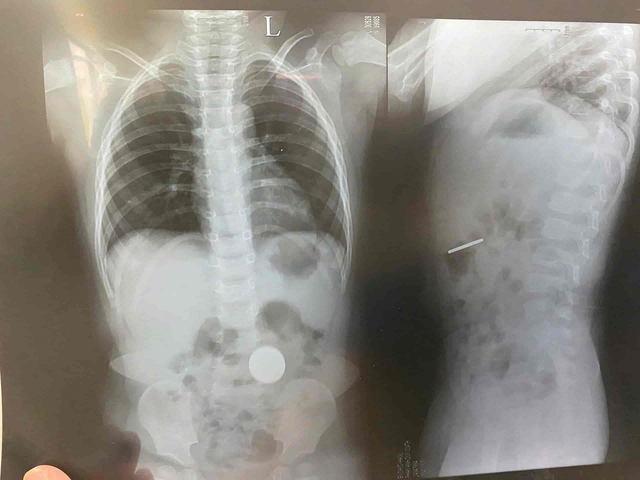

Thông tin ban đầu ngày 6/11, bệnh nhi P.A.D. nhập viện tại Khoa Nhi, Bệnh viện Đại học Y Dược- Hoàng Anh Gia Lai với triệu chứng ho nhiều, viêm phổi. Qua chụp X-quang kiểm tra về viêm phổi, bác sĩ phát hiện một đồng xu kích thước tầm 3 - 4cm nằm trong dạ dày của bệnh nhi.

Đồng xu trong dạ dày bệnh nhi P.A.D. Ảnh: ĐVCC.